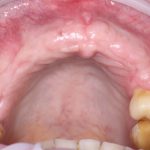

В общем, так и получилось. Уж не помню, почему я наобещал пациентке, что мы поставим ей имплантаты одновременно с остеопластикой. Но я наобещал. И, когда увидел клиническую картину в полости рта:

у меня появились серьезные сомнения, смогу ли я выполнить своё обещание. Вот только не спрашивай меня «Вот чо, сложно было по КЛКТ посмотреть?». Я же не спрашиваю тебя, где ты был в 2013 году, и сделал ли ты домашку. Но, в целом, план операции у нас не поменялся. Как и было оговорено, мы проведем остеопластику с одновременной имплантацией в боковом участке нижней челюсти справа.

Кстати, обрати внимание на ширину альвеолярного гребня (левая картинка). Она чуть меньше 3 мм. Это объясняет, почему я засомневался в возможности установки имплантатов одновременно с остеопластикой. Понятно и без КЛКТ.